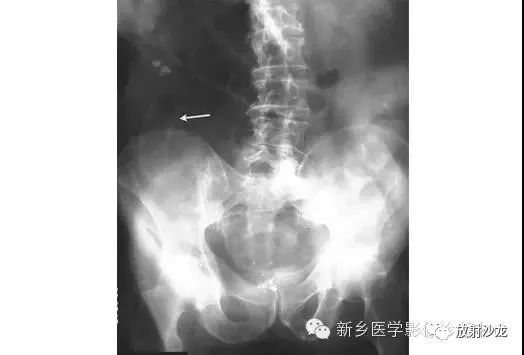

上图为一58岁男性,因1周前非特异性消化不良,行上消化道钡餐检查,做的腹部平片。患者最初表现为不确切的腹部不适和便血。现在又出现了腹痛和腹膜炎。箭头所指的典型表现是什么,诊断是什么?

箭头指向缺血穿孔性肠病患者的浅浮雕征。这也被称为双壁征或Rigler征。通常仅一侧肠壁可以看到。当双侧都能看到时,它表示腔内和腔外都有气体。当病人腹痛症状逐渐加重,肠壁穿孔是很有可能的。该患者手术过程中发现肠道脾曲缺血穿孔性肠病。